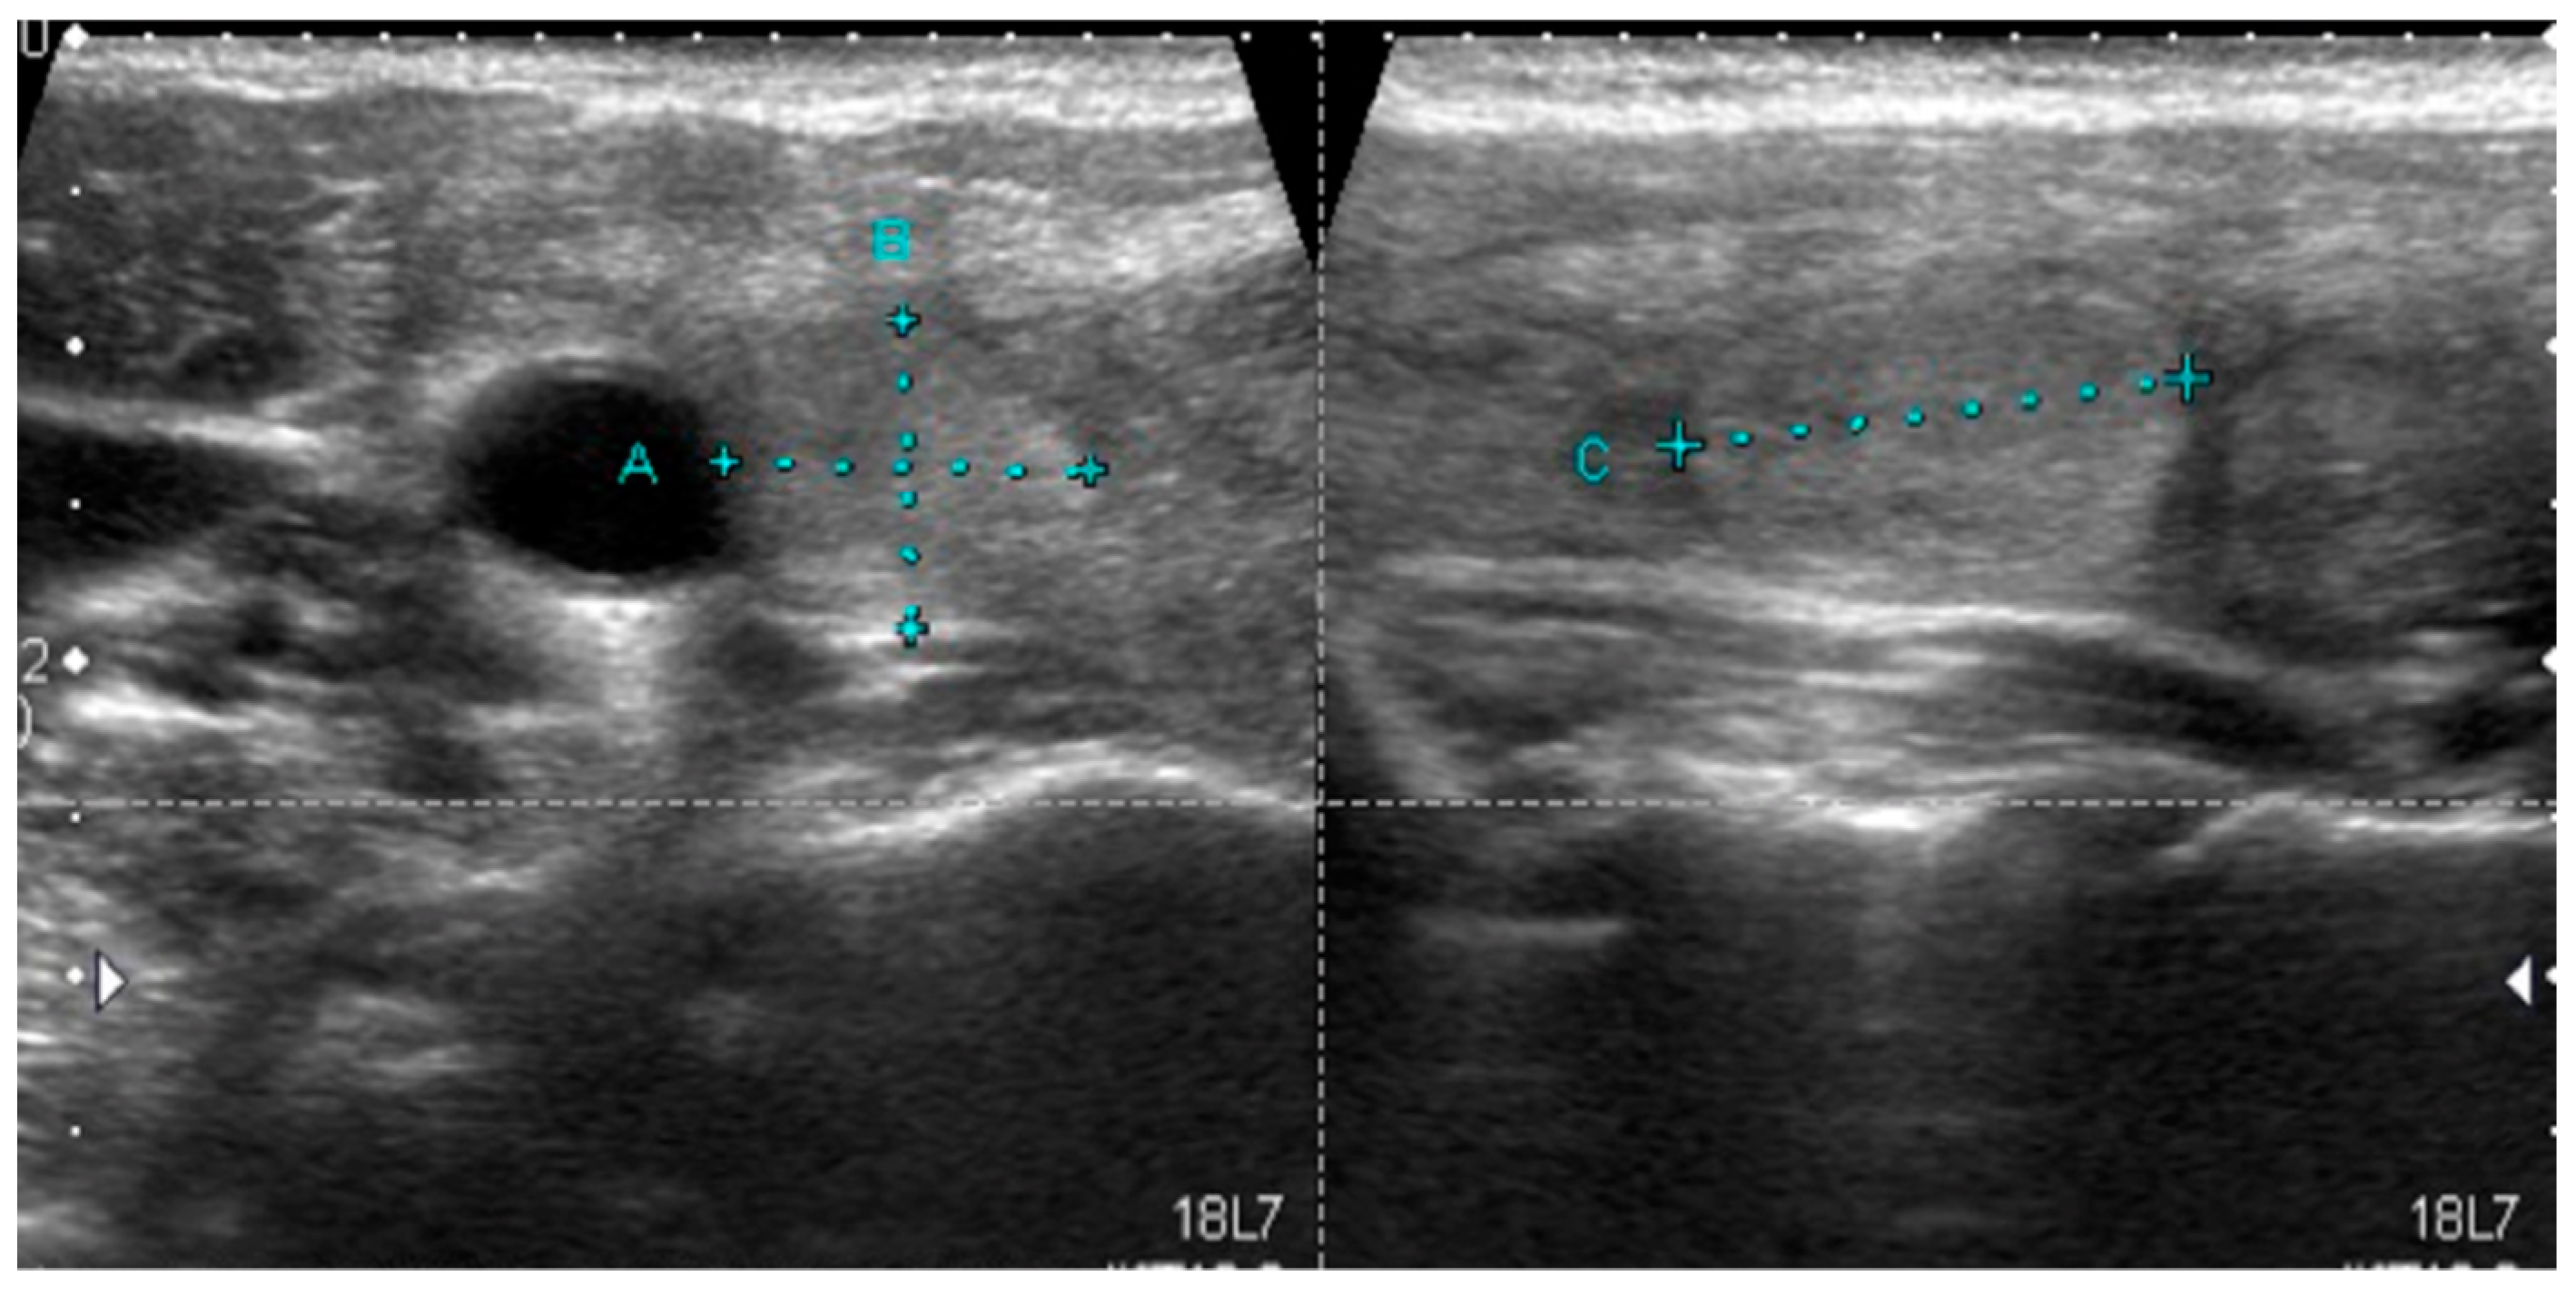

A sonographic pattern typical for PTCs bearing the BRAFV600E mutation is presented in Figure 1.

Figure 1.

Typical sonographic pattern of a BRAFV600E-positive papillary thyroid carcinoma hypoechoic lesion with poorly defined irregular margins and microcalcifications.